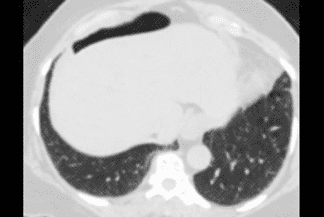

Descrição das imagens: Tomografia computadorizada do abdome evidenciando a interposição colônica no hipocôndrio direito.

Sinal de Chilaiditi: Descrição rara do posicionamento do intestino entre o fígado e o diafragma.

• Radiografia de abdome: I nterposição de gás (em geral, gás de uma laça colônica) entre fígado e o diafragma direito; podemos ver a haustração colônica, confirmando o sinal radiológico;